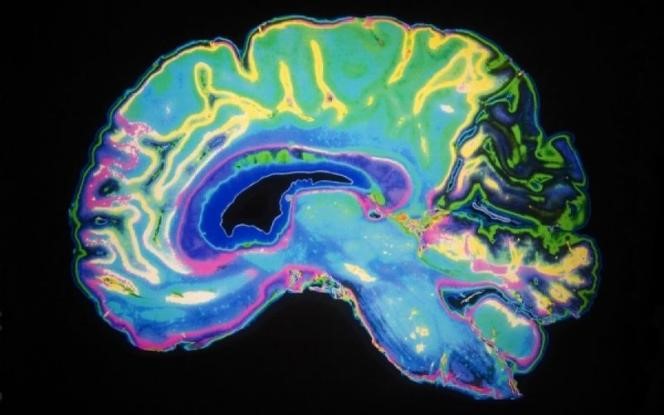

Τι συμβαίνει στον εγκέφαλο ενός ατόμου με κατάθλιψη

Μελέτες δείχνουν ότι ο ιππόκαμπος του εγκεφάλου σε ένα άτομο με κατάθλιψη είναι μικρότερος σε μέγεθος από το κανονικό. Ο ιππόκαμπος είναι η περιοχή του εγκεφάλου που ελέγχει τα συναισθήματα, τη μνήμη και τη μάθηση.

Όσο περισσότερο διαρκεί η κατάθλιψη, τόσο περισσότερο συρρικνώνεται ο ιππόκαμπος. Το στρες συμβάλλει καθοριστικά στον ελλιπή σχηματισμό νέων νευρώνων σε αυτήν την περιοχή του εγκεφάλου.

Όταν όμως ενεργοποιείται ο σχηματισμός νέων νευρώνων και αποκαθίστανται οι βλάβες, η διάθεση βελτιώνεται. Αρκετά από τα φάρμακα που χρησιμοποιούνται σήμερα για την αντιμετώπιση της κατάθλιψης επηρεάζουν έμμεσα την ανάπτυξη των εγκεφαλικών κυττάρων.